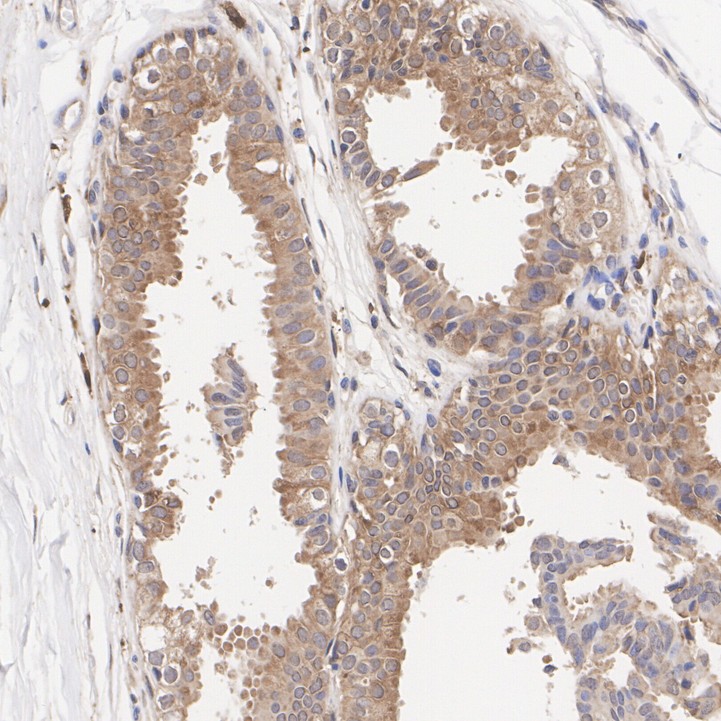

Catalog# HA723483

Livin Recombinant Rabbit Monoclonal Antibody [PSH12-72]

IHC-P